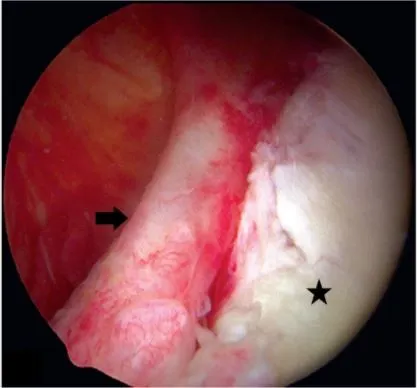

在傷後幾個禮拜後的回診,陳女士提到右肩膀上舉時有比過去無力,且右肩在夜間常有脹痛感,在經過核磁共振及局部診療後,陳女士被診斷為肩關節唇併旋轉肌腱撕裂傷,由於肩部損傷在沒有修補的情況下,復健及藥物治療下進步有限,在骨科醫師的建議下,陳女士接受肩關節鏡手術修補關節唇與旋轉肌,術後三天開始進行被動關節活動,在術後一個月後開始主動式復健訓練,在經過幾個月努力後,陳女士的右肩膀終於恢復到接近左肩的狀況。